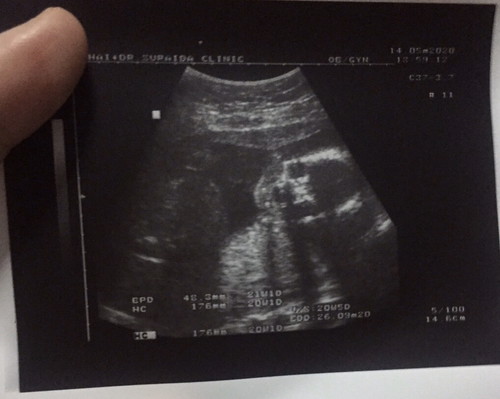

ทีมลูกสาวค่ะ กำหนดคลอด 26 กันยายน ? รอบนี้หันหน้ามาให้เห็นหน้าชัดๆๆ โครงรูปหน้าเหมือนพ่อมาก หนูจะออกมาได้พ่อเต็มๆเลยหรอลูก ??♥️